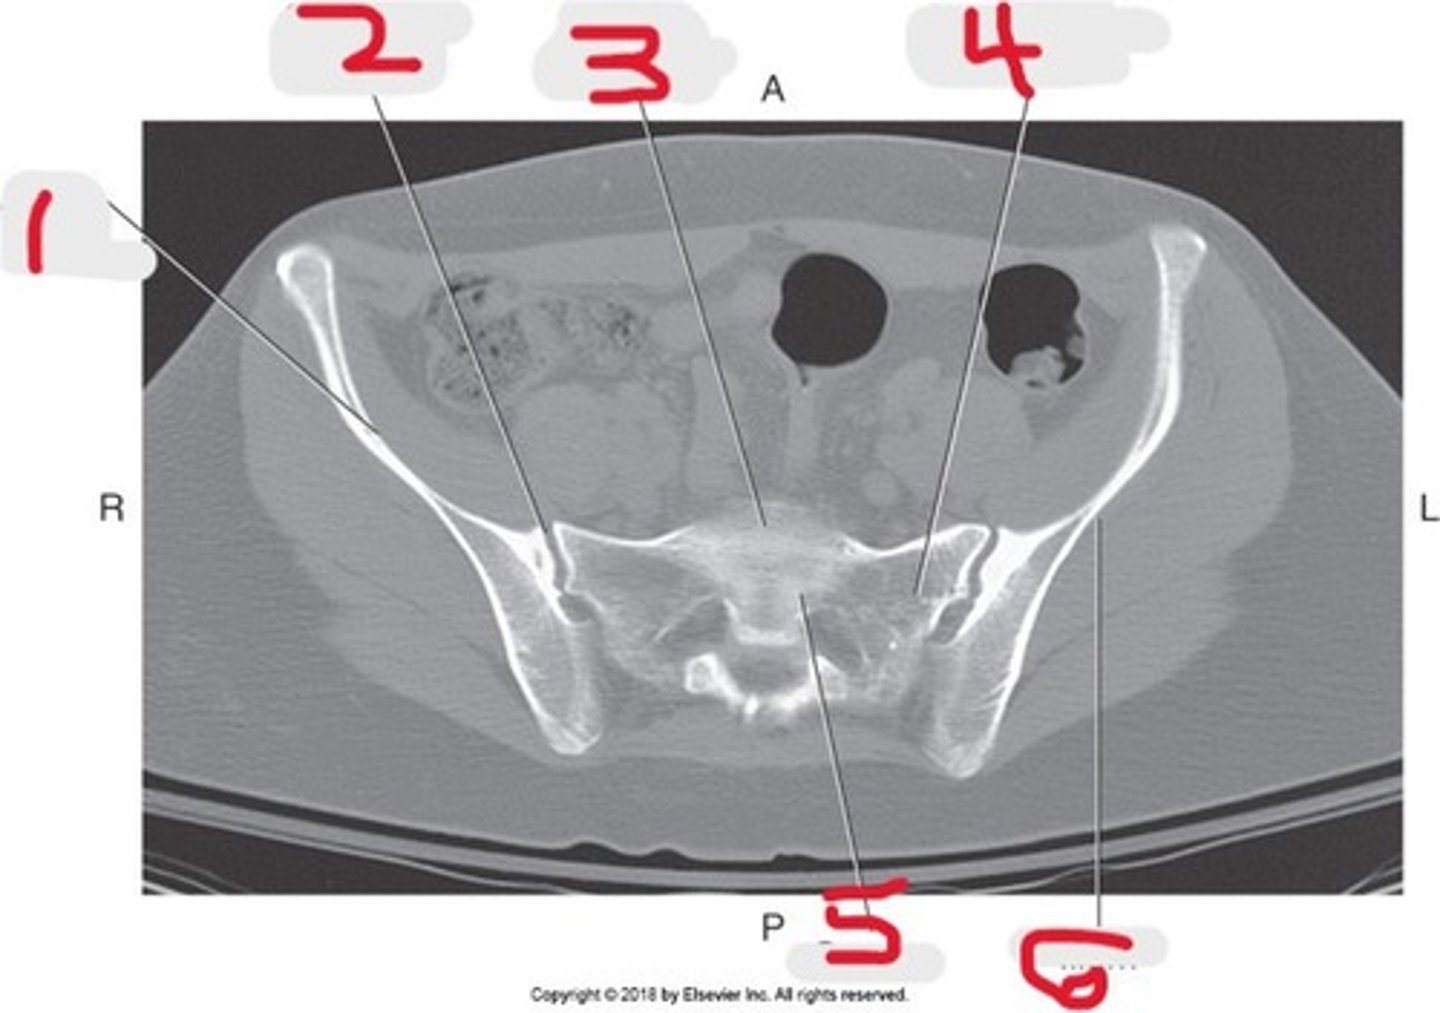

1) Ala of ilium

2) SI joint

3) Sacral promontory

4) Lateral mass of Sacrum

5) Sacrum

Name all numbered structures